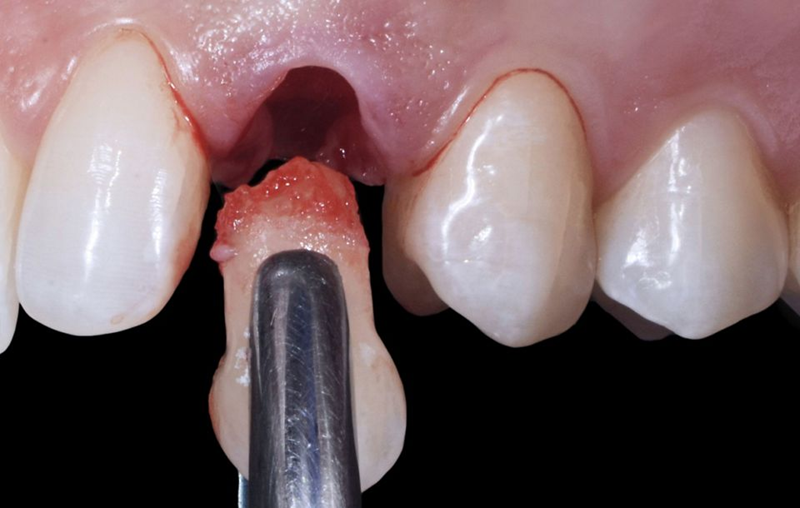

患者在犬尖对应的区域进行了局部麻醉浸润(图25)。乳牙的拔除过程非常简单,牙根几乎完全被吸收(图26-28)。

Fig. 25: Anesthetic infiltration in the area corresponding to the canine apex.

Fig. 26: Plier in position for the extraction procedure.

Fig. 27: The extraction resulted in a simple procedure being the root of...

Fig. 28: Occlusal view of the extraction socket.